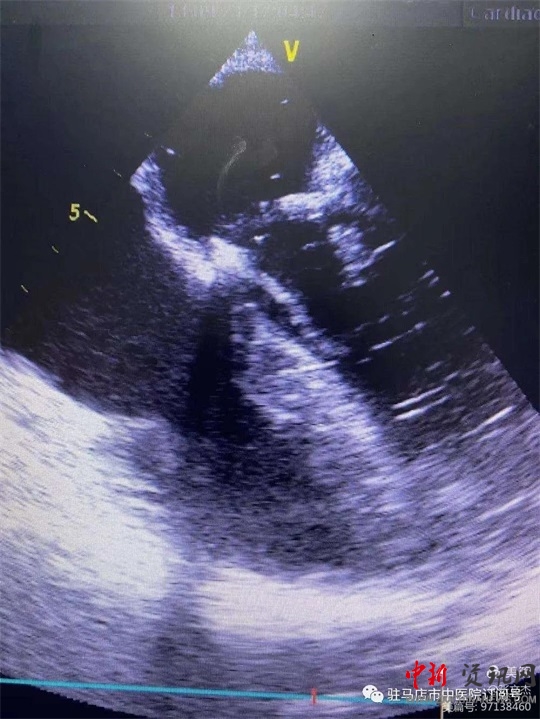

術(shù)前經(jīng)食道心臟超聲